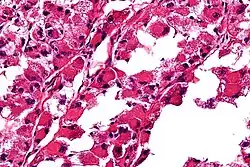

| Micrograph of an alveolar soft part sarcoma, showing the characteristic alveolar-like architecture and cells with eccentric nuclei and abundant eosinophilic cytoplasm. H&E stain. | |

ASPS' histomorphologic features include an alveolar-like pattern at low magnification and the presence of large cells with abundant eosinophilic cytoplasm and eccentric nuclei. Calcifications are commonly present, as may be seen with slow-growing neoplasms.